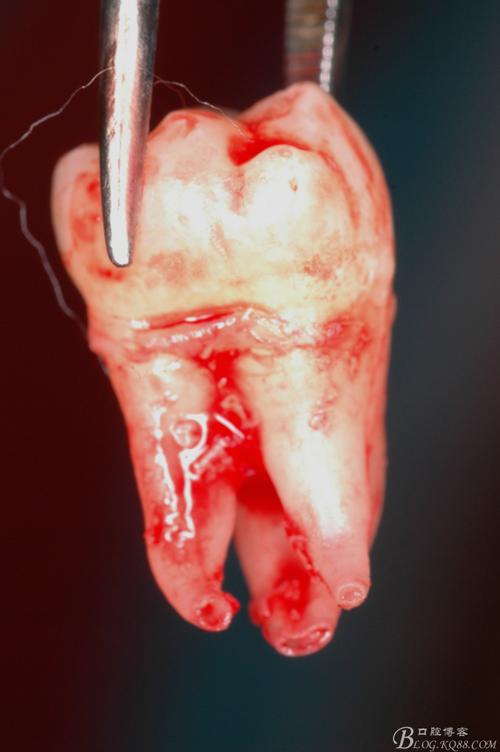

向远中弯曲的牙根.

牙根分叉病变图片

牙根分叉图片

根分叉

牙根图片